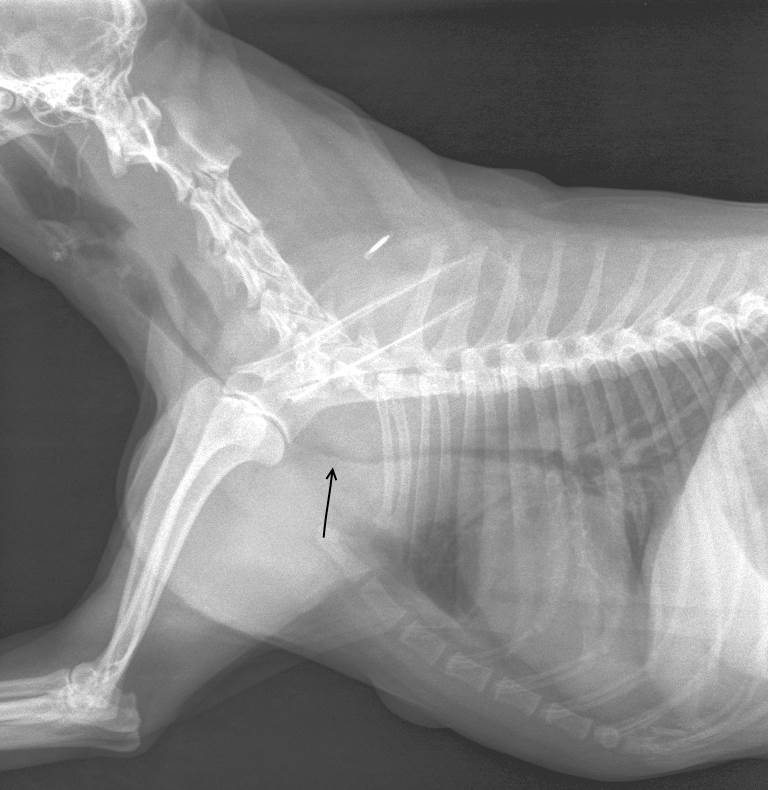

צילום רנטגן מאפשר אבחנה של המצב. במידה ולא רואים את קריסת הקנה בצילום אין האבחנה נשללת, מאחר והקריסה היא דינמית בחלק מהמקרים, ומתרחשת רק בחלק ממחזור הנשימה (שאיפה / נשיפה).

בצילום המצורף ניתן לראות את האזור בו קנה הנשימה מוצר מאוד (חץ שחור) והקוטר שלו באזור הלא תקין הינו 2-3 מ"מ בלבד.